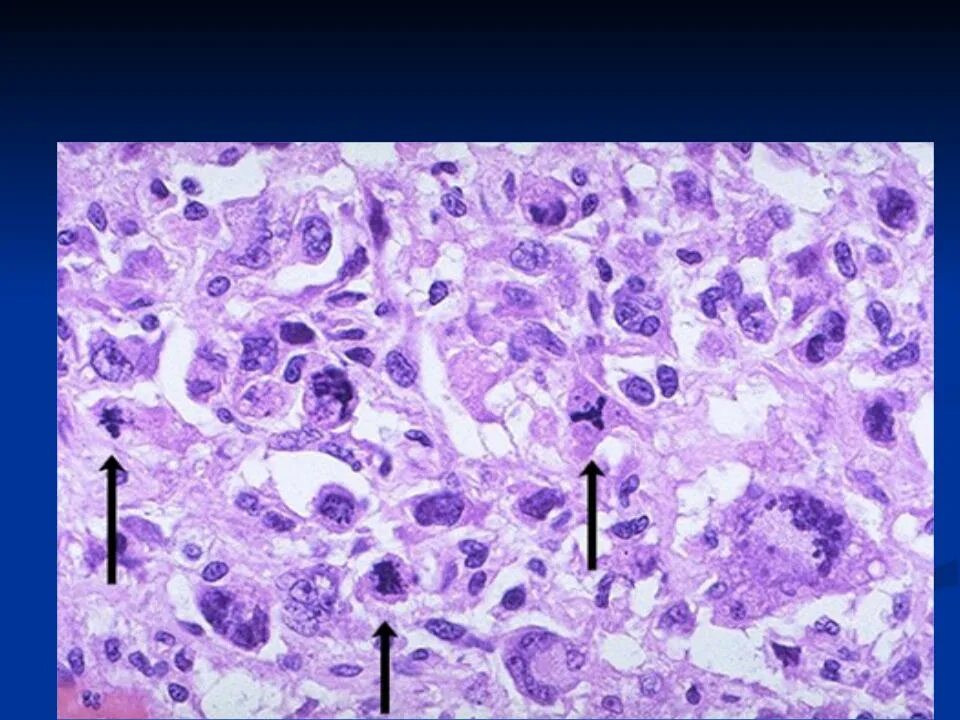

Атипичные клетки в гистологии